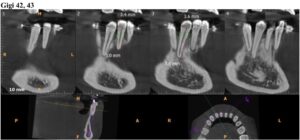

前回1月18日に歯石取りなどを終えており、歯茎の状態も特に悪化していることもなかったので、2月21日にレントゲン検査 (CBCT) 実施後、2月28日と3月28日に歯肉移植手術(下の歯左右2番と3番計4本に対し、左側と右側の2回に分けて行う)を実施することになりました。

歯肉移植手術1回目(手術方式:CBCT、術部:左下2番・3番、手術時間1.5時間)

また、2回目の歯肉移植手術の方式は、ADMという方式で実施することになりました。1回目のCBCTは上顎からの痛み・出血を伴うこと、今回上手く行かなかったためだそうです。

歯肉移植手術2回目(手術方式:ADM、術部:左下2番・3番と右下2番・3番、手術時間2時間)

レントゲン検査 (CBCT) の結果をもとに、歯肉移植手術を2回(2月28日と3月28日)に分けて実施しました。

手術自体は麻酔をするので痛みはなく、少し出血がある程度でした。手術時間は1回あたり90分で、手術後は歯磨きを強くしすぎないことや熱いものを飲まないよう注意し、指定された痛み止めの薬を1日1回、3日間飲み続けるようにとのことでした。